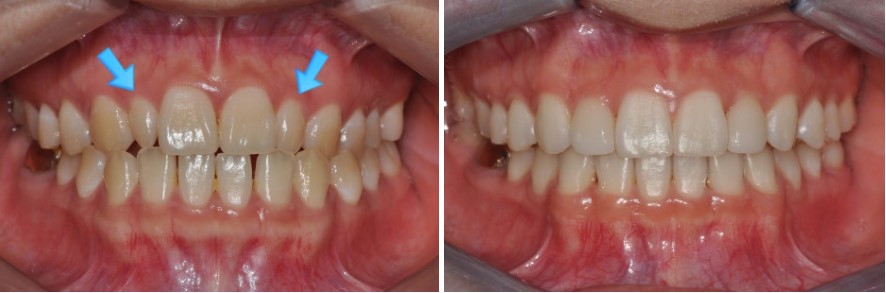

예를 들어,

돌출과 치아 배열 때문에 내원하신 30대 여성 환자분의 경우,

이때 치간삭제를 시행하고 공간을 다시 닫아 주면서

블랙 트라이앵글이 완전히 사라지지는 않더라도

눈에 띄게 크기가 줄고, 치아 사이가 더 긴밀하게 붙어 보이는 효과를 얻을 수 있습니다.